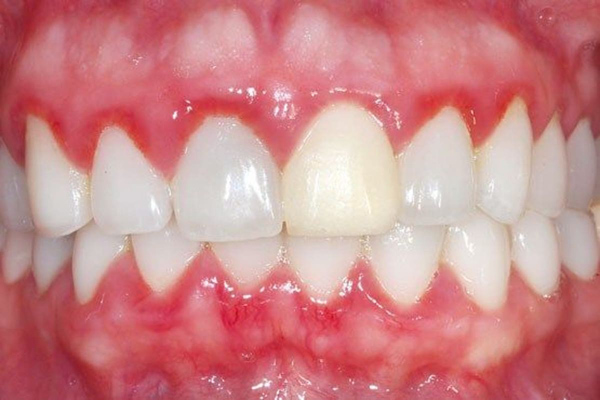

Răng cửa bị mẻ thường tạo ra các cạnh sắc nhọn có thể gây tổn thương cho nướu xung quanh. Sự tổn thương này có thể dẫn đến viêm nướu, chảy máu nướu và các vấn đề nha chu khác. Nếu không được chữa trị kịp thời, viêm nướu có thể tiến triển thành các tình trạng nặng hơn như túi nha chu, tiêu xương ổ răng và mất răng, làm suy giảm sức khỏe toàn diện của hàm răng và nướu.

Viêm nướu